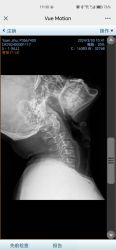

无标题 无名氏 2025-05-21(三)17:07:13 ID:nUbJLeP [举报] No.66127925 管理

我的劲椎和假牙……

>>No.66127925

还有一张是颈椎笔直没一点弧度的,但是假牙没太拍到

增生比较多,曲度有点直

平常还是少低头点( ゚ 3゚)

>>No.66127949当时是头晕,恶心,去医院拍了片子也是说,只能自己注意,少低头,后面就是上班把屏幕垫高

>>No.66128011

睡觉的时候把枕头垫到肩膀下,就是左手抱右肩一开始摸到的那个位置的水平线

枕头一个拳头高,最好偏硬一点

肥哥的片子没写年龄,但是这个颈椎增生确实要注意一下了,头晕可能是歪头之类的导致的寰枢关节不对称(`・ω・)